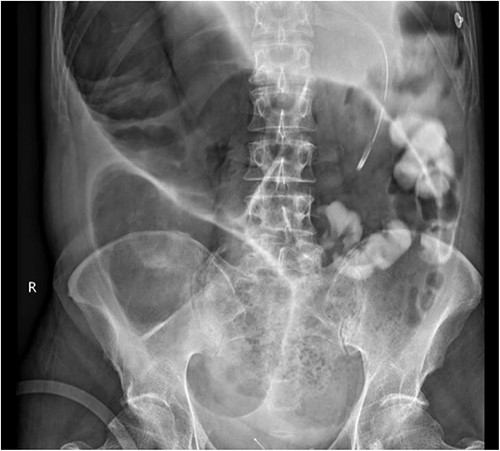

A week later, the patient reported new central abdominal pain with associated nausea and his last bowel action was almost 1 week prior. On examination, his abdomen was distended with generalized tenderness, but there was no peritonism. He was subsequently treated with regular oral laxatives, but with no improvement. A computed tomography (CT) abdomen and pelvis with oral and intravenous contrast was performed, which demonstrated marked faecal loading in the ascending and transverse colon with no convincing evidence of mechanical bowel obstruction (Fig. 1).

(a) Coronal and (b) axial views of CT abdominal pelvis, with oral and intravenous contrast demonstrating significant faecal loading in ascending colon and proximal to mid-transverse colon.